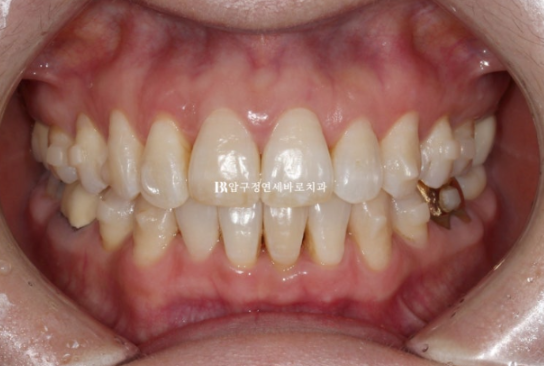

50대 환자분께서 앞니가 점점 뻗치고 틀어져서 교정을 위해 내원하셨습니다.

오래 전 발치교정을 이미 끝냈는데, 나이가 들면서 점점 앞니가 틀어져 앞니 부분교정을 위해 오셨습니다.

위 앞니 두개가 튀어나와있고 회전이 되어있습니다.

정식용어는 아니지만 이것을 나비치아 라고 부릅니다.

이 정도면 인비절라인 라이트로도 충분히 교정이 가능합니다.

배열이 가지런해졌고 소량의 치간삭제를 통해 블랙트라이앵글도 줄었습니다.

단 위 앞니 높낮이 단차가 있어서 이 부분을 추가장치에서 해결하기로 했습니다.